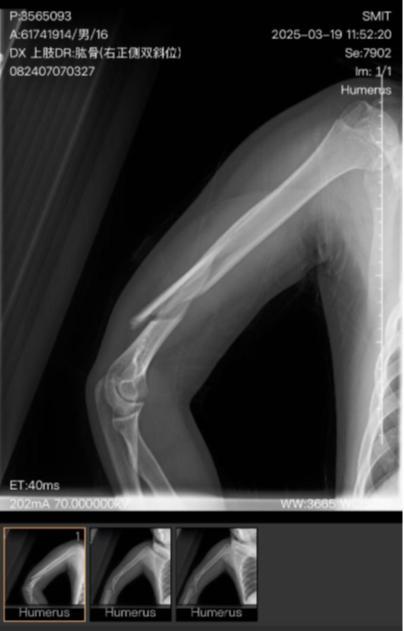

秦皇岛市第一医院一份手术记录显示,3月21日,小明因右肱骨粉碎性骨折、右桡神经损伤进行手术治疗。

日前,记者接到河北秦皇岛的周先生反映,其子小明(化名)是秦皇岛市职业技术学校的高一学生,今年3月19日早上8时20分左右,小明因前一晚在宿舍说话被罚站,最终被教工扔起摔伤,造成右胳膊粉碎性骨折,右桡神经损伤。

4月14日,秦皇岛市公安局山海关分局出具《鉴定意见通知书》显示,小明的人体损伤程度达到轻伤一级。16日,山海关分局出具《立案告知书》,称小明被故意伤害一案符合立案条件,现已立案。